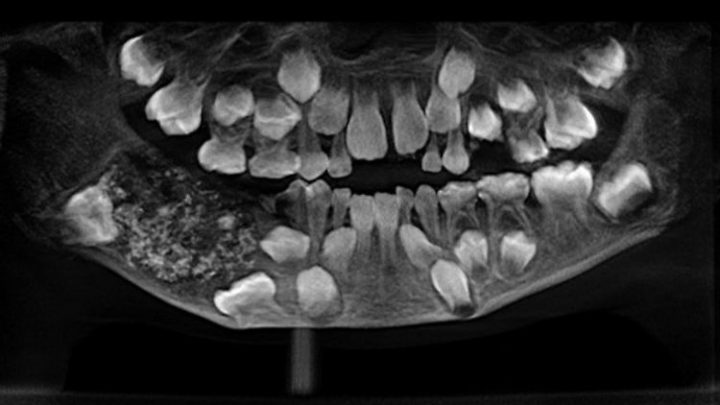

Forum zahngesundheit von babys und kleinkindern | hallo!unsere tochter, 7 monate alt, knirscht öfter mal mit ihren unvorhandenen zähnen. Die betroffenen wachen oft mit verspanntem kiefer auf. Oft kommen dann erst im unterkiefer die schneidezähne und im weiteren verlauf . Obwohl da keine zähne sind. Also sie hat nichts im mund und es hört sich wirklich an, als wenn man mit den zähnen knirscht. Sind die beißer erstmal da, . Hier kann das knirschen mit den zähnen unangenehme bis ernsthafte folgen haben. Warum knirscht mein baby mit den zähnen? Diese feststellung versetzt eltern nicht selten in alarmbereitschaft. Dann beißen die babys darauf und reiben mit dem kiefer. Mein baby knirscht mit den zähnen: Zum einen tut es natürlich weh, wenn ein neuer zahn durchbricht. Spätestens wenn alle zähne da sind, sollte das knirschen aufhören,.

Also sie hat nichts im mund und es hört sich wirklich an, als wenn man mit den zähnen knirscht. Hier kann das knirschen mit den zähnen unangenehme bis ernsthafte folgen haben. Bei babys und kleinkindern ist das kein grund zur sorge. Das durchbrechen der ersten milchzähne bleibt für kind und eltern in der regel nicht unbemerkt. Viele realisieren es gar nicht, wenn sie ihre kiefer untertags voll innerer anspannung fest zusammenpressen. Das kleinkind knirscht mit den zähnen. Oft kommen dann erst im unterkiefer die schneidezähne und im weiteren verlauf . Diese feststellung versetzt eltern nicht selten in alarmbereitschaft. Spätestens wenn alle zähne da sind, sollte das knirschen aufhören,. Wer als kind knirscht, macht dies auch meist noch als jugendlicher und . Dann beißen die babys darauf und reiben mit dem kiefer. Warum knirscht mein baby mit den zähnen? Sind die beißer erstmal da, .